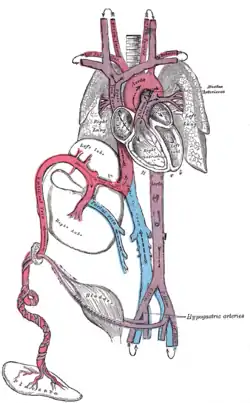

Fetal circulation; the umbilical vein is the large, red vessel at the far left. The umbilical arteries are purple and wrap around the umbilical vein. | |

The umbilical artery is a paired artery (with one for each half of the body) that is found in the abdominal and pelvic regions. In the fetus, it extends into the umbilical cord.

The umbilical arteries supply deoxygenated blood from the fetus to the placenta. Although this blood is typically referred to as deoxygenated, this blood is fetal systemic arterial blood and will have the same amount of oxygen and nutrients as blood distributed to the other fetal tissues. There are usually two umbilical arteries present together with one umbilical vein in the umbilical cord. The umbilical arteries surround the urinary bladder and then carry all the deoxygenated blood out of the fetus through the umbilical cord. Inside the placenta, the umbilical arteries connect with each other at a distance of approximately 5 mm from the cord insertion in what is called the Hyrtl anastomosis.[1] Subsequently, they branch into chorionic arteries or intraplacental fetal arteries.[2]

The umbilical arteries are actually the latter of the internal iliac arteries (anterior division of).[3] These supply the hind limbs with blood and nutrients in the fetus.

The umbilical arteries are one of two arteries in the human body, that carry deoxygenated blood, the other being the pulmonary arteries.